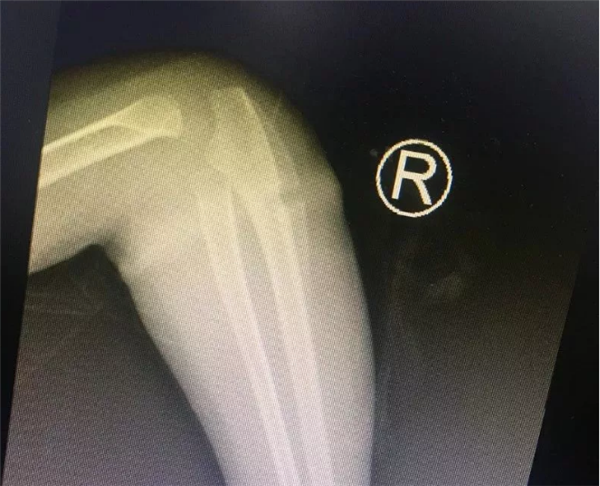

几天前,困扰安徽临泉乐乐一家人半年之久的手臂“圆环”事件终于真相大白了。难以想象的是一根很普通的橡皮筋竟然偷偷“长”进孩子的肉里!最终,浙大儿院湖滨院区骨科叶文松副主任在孩子的手臂中找出橡皮筋,解决了